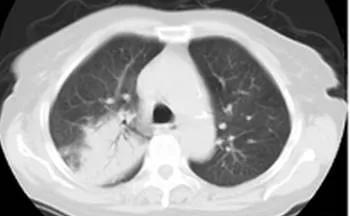

肺炎支原体肺炎主要临床表现为反复发热、咳嗽,肺部体征与临床表现及影像学不一致。影像学表现包括肺间质浸润、肺叶实变和肺门淋巴结肿大。部分患儿有多系统受累,如麻疹样或猩红疹、心肌炎、溶血性贫血、心肌炎或心包炎、格林-巴利综合征等。

选择支气管镜治疗的指征:(1)经常规检测和治疗,疗效差,病原体不明,怀疑感染特殊病原体、混合病原体或耐药菌。(2)非感染性原因可能并存,如气道异物、新生物、气道狭窄等。(3)有明显气道阻塞征象时:影像学提示肺不张、气道阻塞引起的单侧肺气肿、纵隔气肿、单侧或双侧肺实变,尤其是支气管充气征、树芽征消失等小气道疾病。(4)肺炎支原体、腺病毒、流感病毒等感染或某些重症细菌性肺炎有梗阻迹象。(5)使用抗感染药物。